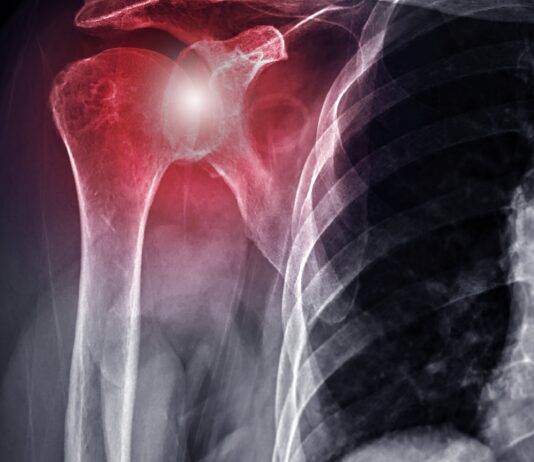

Artrosi del ginocchio: la fisioterapia digitale migliora dolore e funzione

Le tecnologie digitali stanno assumendo un ruolo crescente nella riabilitazione dei pazienti con patologie muscoloscheletriche. Una nuova revisione...